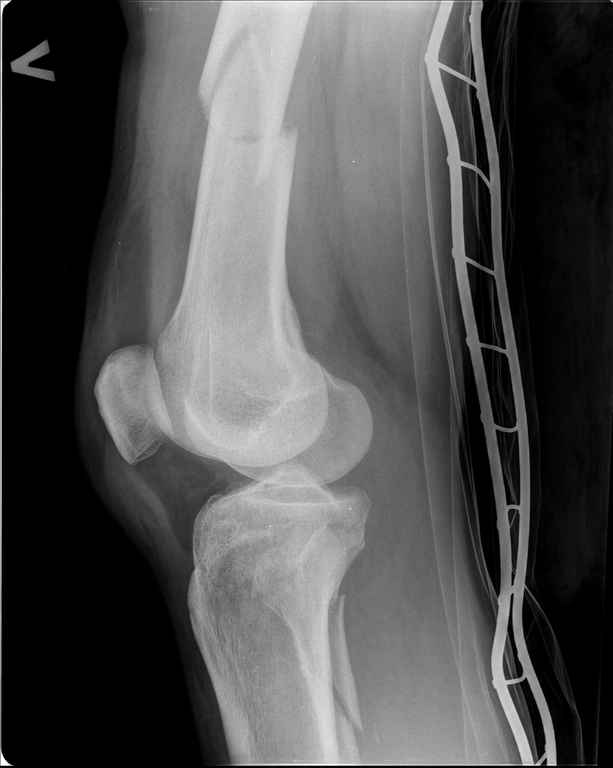

Ds: ТСТ. ЗЧМТ. СГМ. ЗТГК. О/фрагментарный перелом левого бедра. З/оскольчатый перелом с\3 левого плеча. Перелом левого локтевого отростка. З/перелом наружного мыщелка б/берцовой кости в/3 м/берцовой кости левой голени. при поступлении, ПХО раны левого бедра( рана 1х1см по наружной поверхности бедра в с/3) налажено скелетное вытяжение , и гипсовая лонгета на левую в/конечность. Находился в реанимации. 17.02.11 был прооперирован: БИОС левого плеча, о/синтез левого локтевого отростка по Веберу, БИОС левого бедра (длинная версия Fi-Can Sanatmetal диаметр 10мм), мыщелок голени трогать не стали.при остеосинтезе бедра возникли трудности при закрытй репозиции перелома в н/3, в связи с чем решили открыться внизу , отрепонировали без особого труда и выполнили блокирование во фронтальной плоскости 3-мя винтами + 1 винт спереди гвоздя (промазал). Убрал костодержатель, все нормально, контроль ЭОПом стояние отломков нормальное, зашились. На контрольной R-мме на утро выявлено вторичное смещение дистального отломка. Левая нога по сравнению со здоровой удлиннена до 2,5см( это за счет вальгусной установки гвоздя в проксимальном отделе, боялся свалиться на варус). Теперь думаем как поправить положение отломков в н/3, и зафиксировать так чтобы не съехало. Наше предложение расшиться в н/3 бедра, разблокироваться, перелом отрепонировать вновь и установить 1или 2отклоняющих винта в сагитальной плоскости, затем заблокироваться во фронтальной плоскости снова. Помогите советом, как выйти достойно из сложившейся ситуации. Заранее спасибо.

Важно установить из-за чего произошла вальгусная деформация дистального отломка (при условии, что на операционном столе после дистального блокирования её не было). Если взять в руки стержень и ввести в дистальное круглое отверстие блокирующий винт, то из-за разности в диаметрах блокирующего винта и диаметра блокирующего отверстия в стержне, возможно отклонение стержня во фронтальной плоскости до 13 градусов в каждую из сторон. Если второе отверстие для блокирования на дистальном конце стержня круглое, проблема «качания» дистального отломка во фронтальной плоскости на одном блокирующем винте при инфраистмальных переломах решается введением второго блокирующего винта во фронтальной плоскости. Если второе блокирующее отверстие овальное, введение второго блокирующего винта во фронтальной плоскости эту проблему не решит (кажется, это ваш случай). В таком случае лучшим решением является введение блокирующего винта в сагитальной плоскости через соответствующее отверстие стержня (это всегда лучший вариант). Однако в выбранном стержне такого отверстия нет. Поэтому мы бы поступили следующим образом. Удалили бы все дистальные блокирующие винты. Выполнили бы открытую репозицию дистального перелома на стержне с ликвидацией вальгусной деформации. Мне представляется, что это технически выполнимо, поскольку стержень не погружен в мыщелки глубоко и уже произошло вторичное смещение. Перелом предварительно фиксировали бы костодержателем. В качестве противоупора в заглушку стержня необходимо вставить отвёртку. Ударами по костодержателю в проксимальном направлении постарались бы ликвидировать диастаз в вертельной области. Выполнили бы дистальное блокирование двумя винтами во фронтальной плоскости, причём винт в овальном отверстии провели бы по его проксимальному краю. На проксимальном конце дистального отломка максимально близко к месту перелома в сагитальной плоскости провели бы два винта poler по обеим сторонам стержня.